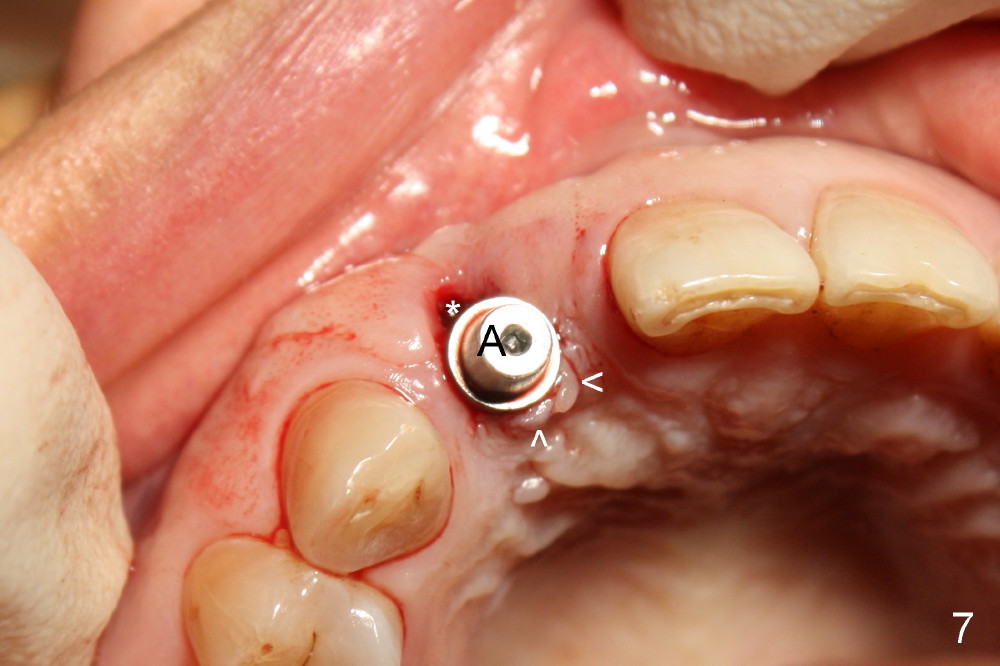

Malpositioned implant in the anterior region is cosmetically unacceptable. Immediate provisional allows us to note the issue immediately. The crown looks too long. Secondly, the provisional is easily dislodged, since the buccal aspect of the angled abutment is over trimmed (Fig.1). The implant (3.8x14 mm), which has been placed 3.5 months, is unexpectedly easily removed by reverse torque (Fig.2). The buccal wall is intact, whereas there seems to be enough bone lingually to place an implant. A small incision is made (Fig.11) so that the gingival tissue can be transferred buccally (Fig.12) and the immediate implant is to be placed palatally (Fig.13 white circle). There is no difficulty forming osteotomy in the palatal wall, followed by inserting 4.5x20 mm tap at the depth of 17 mm (Fig.3,5). But the tap is not palatal enough (Fig.4). By removing more palatal bone, the 4.5x17 implant (Fig.6) appears to be placed palatally enough for restoration (Fig.7; A: abutment; *: buccal gap). The biggest problem is that the palatal flap (Fig.7 arrowheads) cannot be pushed buccally; instead remains palatally. This leads to buccal tissue deficiency (Fig.8). Connective tissue graft is offered, but declined. The patient insists that she has low smile line. Following immediate provisional, mixture of allograft and synthetic graft is placed in the buccal gap (Fig.9). The overbuilt graft is held in place by perio dressing.